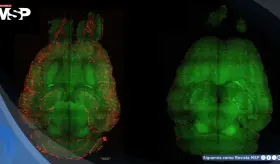

La insulina intranasal logró disminuir marcadores de neuroinflamación en el hipocampo, una región clave para la memoria. Esto sugiere que frenar la inflamación podría ser una estrategia central para proteger la función cognitiva con el paso del tiempo